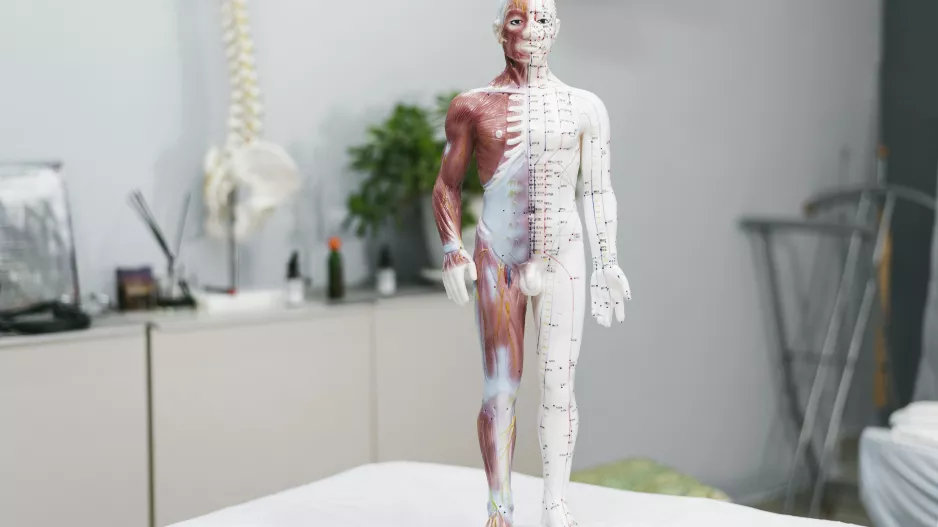

Alergie na mužský sekret trápí ženy i muže: Způsobuje nejen vyrážky, ale i potíže, které byste nečekali